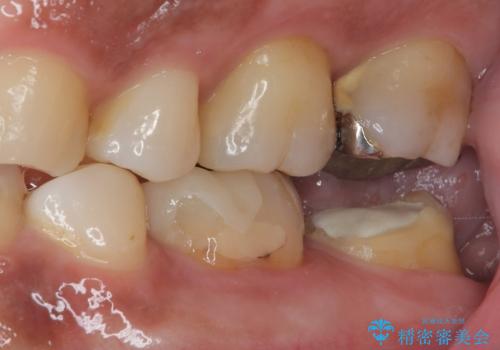

- 他院で「左下の親知らずの手前の歯が虫歯」と診断された患者様の症例です。

診査の結果、下顎左側第二大臼歯の遠心(奥側)に大きな虫歯があり、歯肉の奥深く、骨の縁まで進行している状態でした。

このようなケースでは、虫歯を完全に除去して精密な補綴治療をするのが難しく、長期的な予後が不良となることが多いです。